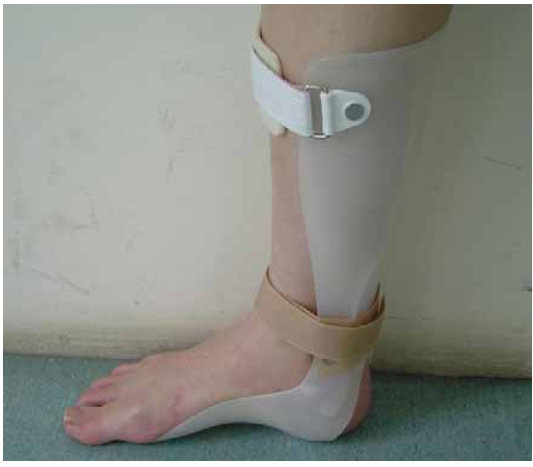

55 圖中的支架不適用於下列何種病人?

(A)扁平足 (B)腦中風 (C)腓神經麻痺 (D)小兒麻痺症